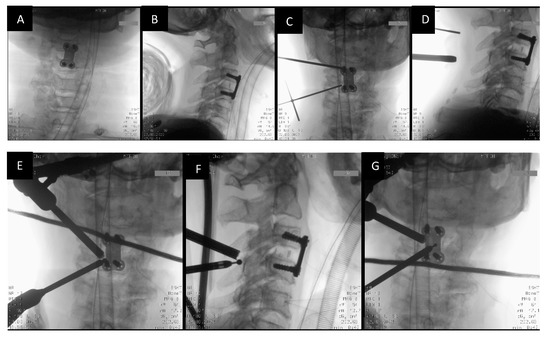

The patient is positioned supine first for the first part of the surgery for Anterior Cervical Discectomy and Fusion. Surgery is performed under General Anesthesia, and the patient is placed onto a radiolucent table. The authors prefer to approach from the right for the anterior approach to the cervical spine. Once Anterior Cervical Discectomy and Fusion are carried out, the patient is then turned prone after the application of the Mayfield clamp (Figure 2A).

Figure 2.

(A): Patient positioned prone after the application of Mayfield clamps after the ACDF procedure, (B): Skin markings 2 cm apart over the pedicle line at the target level C3 lamina.

The surgeon stands on the same side as the pathology (the left side, in this case). Two portals are made with two skin incisions (Figure 2B) of 7 mm in length that are made horizontally on the pedicle under the guidance of C-arm fluoroscopy (Figure 3A–D). Each skin incision for the portal is made at the upper and lower pedicle (C3 and C4), related to the target level. The distance between these two portals is about 2 cm.

Figure 3.

Radiological identification of the portal placement levels with the Image Intensifier. (A,B) show the AP and Lateral views prior to skin marking. (C,D) show skin marking with metal markers in AP and Lateral views. (E,F) show ipsilateral burring using a 3.5 mm spherical diamond burr. (G) shows sublaminar burring of the contralateral side.